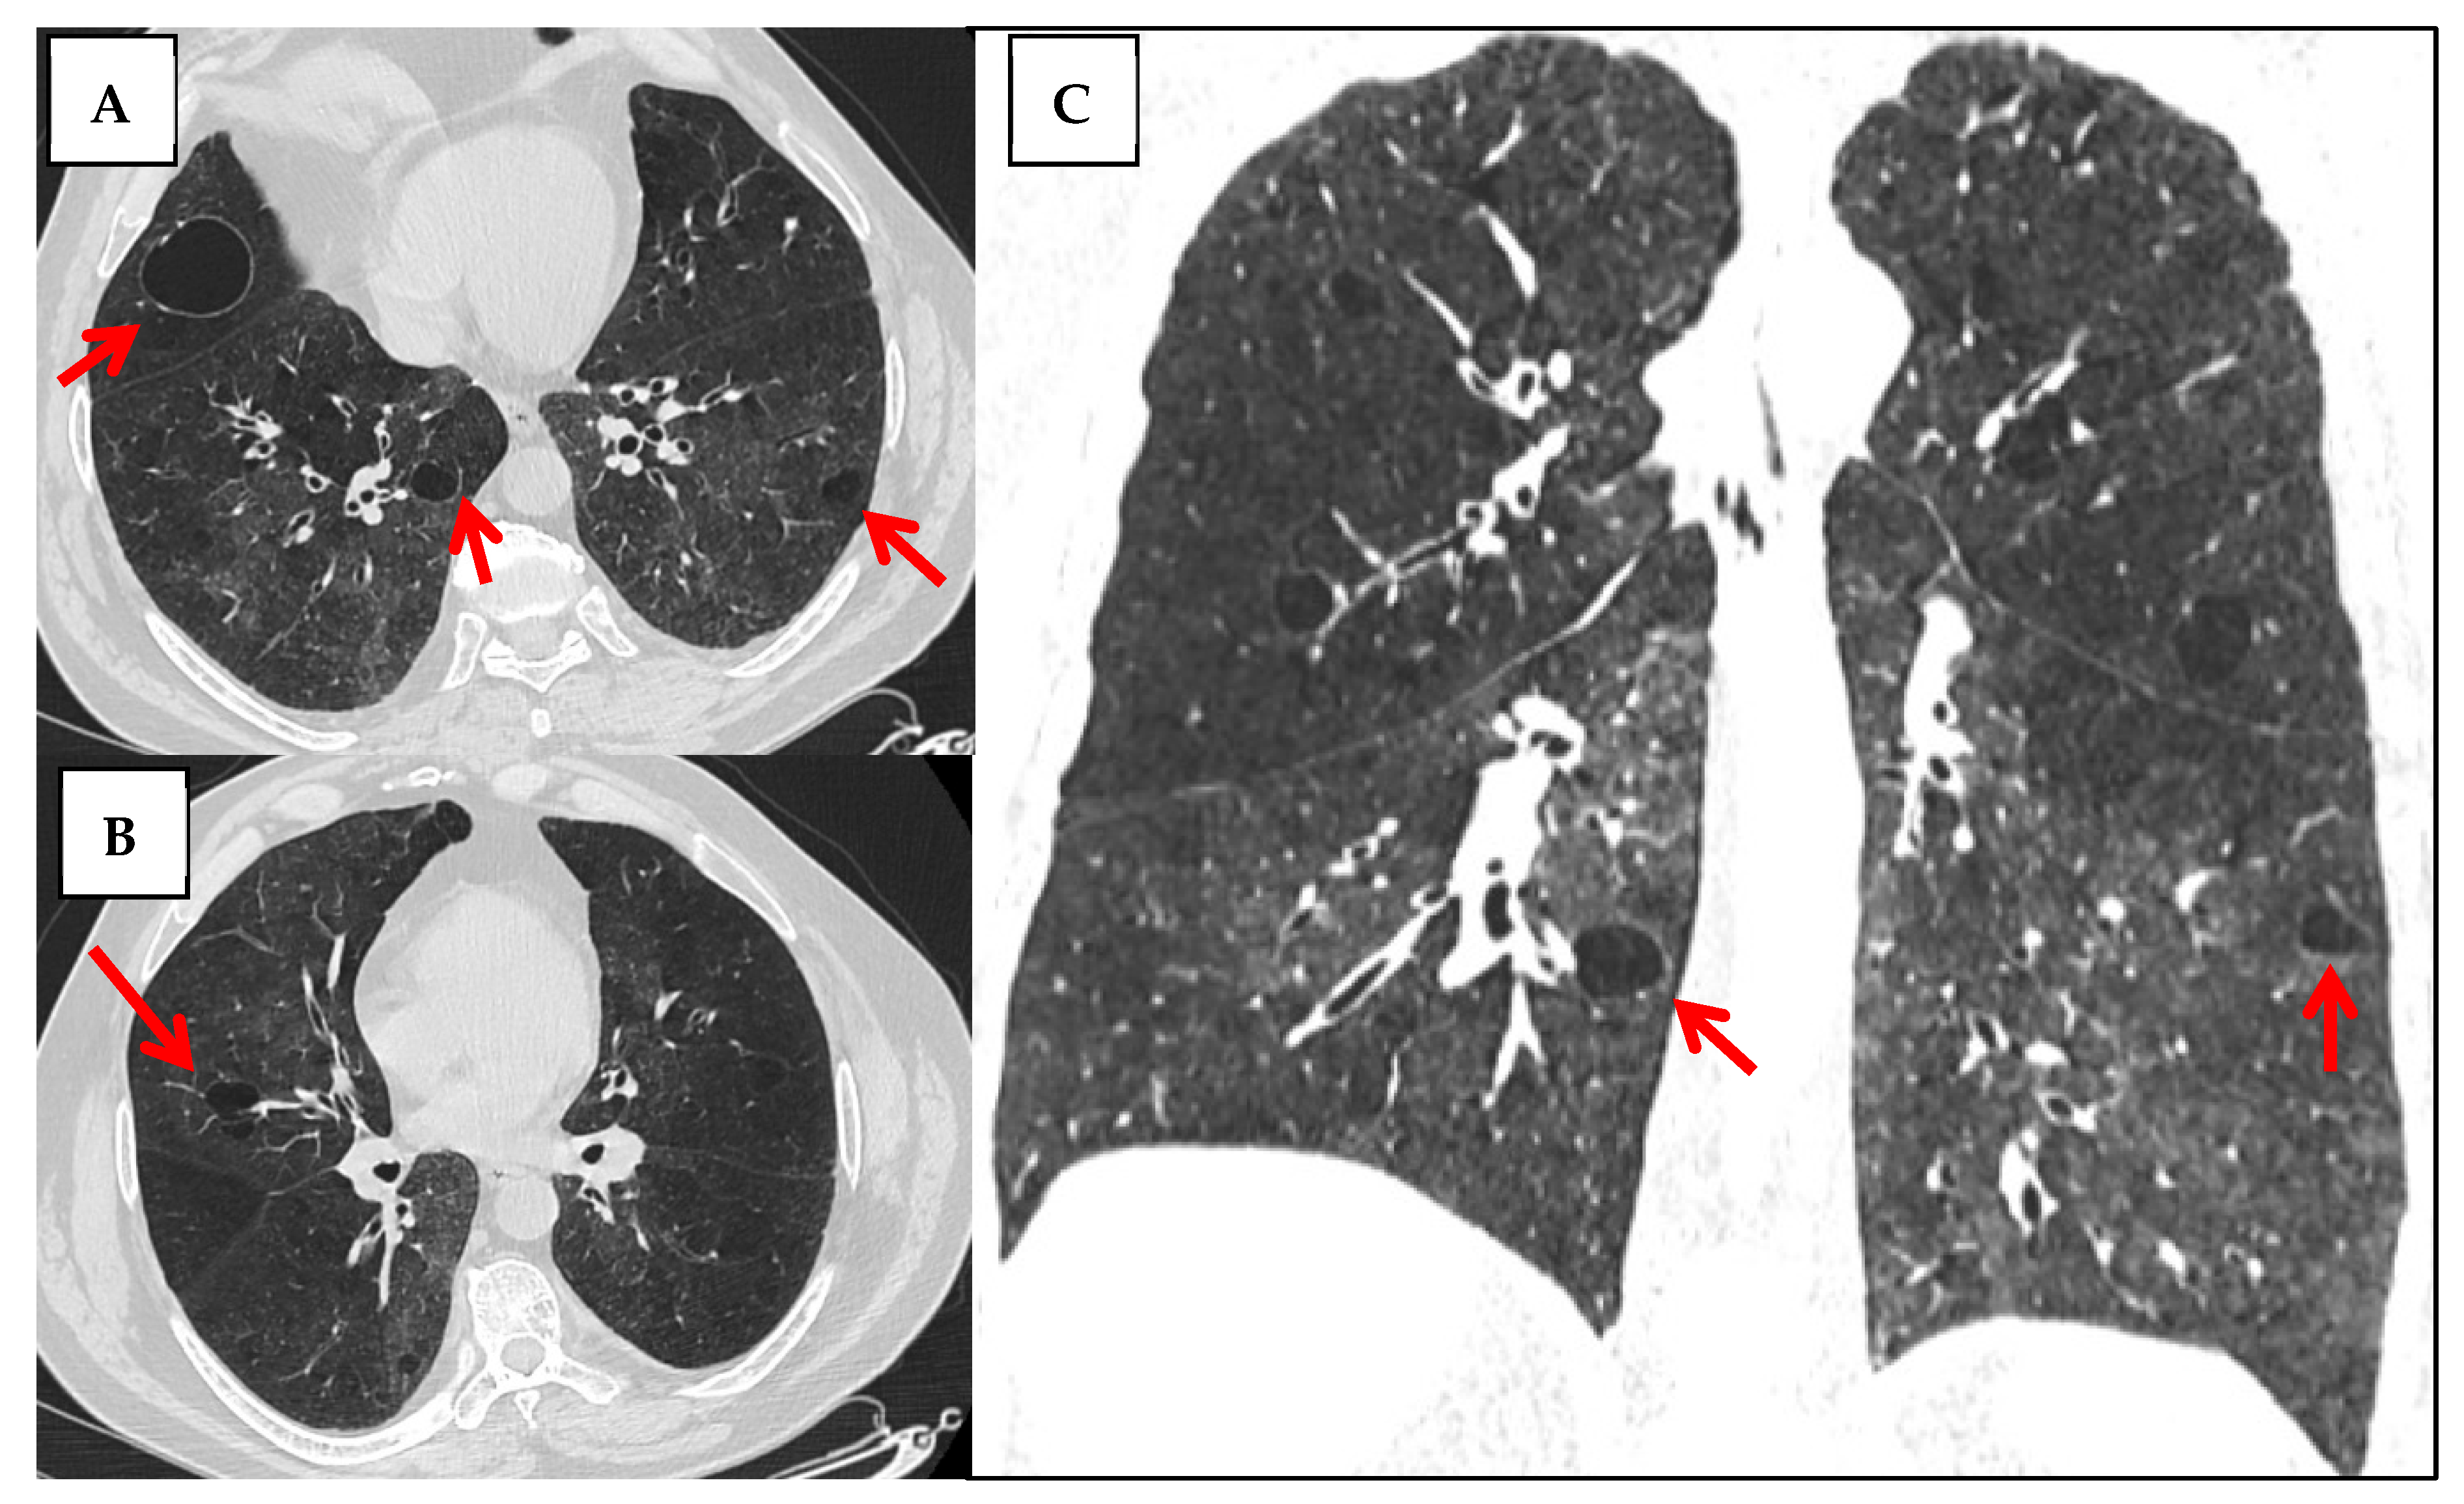

| HRCT patterns | - NSIP (42%) is most common, followed by UIP (11%), and OP/LIP (4% each).  - some studies report higher LIP prevalence (up to 17.4%). - mixed patterns (e.g., NSIP + OP/LIP) are also frequently observed.  | [21,50] |

| Other pulmonary involvement | - cystic lung disease (more common in pSS than other CTDs),  - airway-centered abnormalities (centrilobular nodules, tree-in-bud), bronchiectasis, air trapping, mosaic attenuation—often linked to follicular or constrictive bronchiolitis.  | [21,46,47,48] |